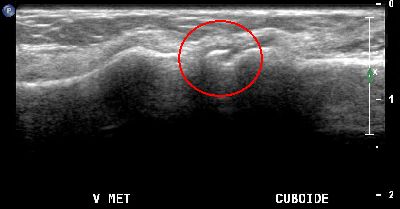

Depressione cuboidea depressione cuboidea 01

Depressione cuboidea depressione cuboidea 02